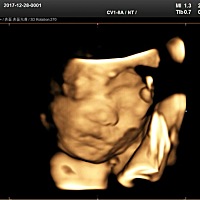

56天还没胎心正常吗